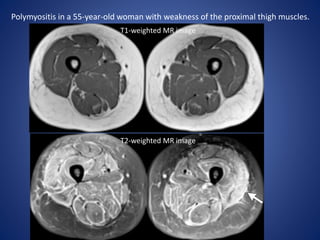

Polymyositis in a 55-year-old woman with weakness of the proximal thigh muscles.

T1-weighted MR image

T2-weighted MR image

Polymyositis in a55-year-old woman with weakness of the proximal thigh muscles. T1-weighted MR image T2-weighted MR image

• #15 Although the thigh muscle bulk and signal intensity are normal on the transverse T1-weighted MR image (a),,, the T2-weighted MR image (b) reveals symmetric regions of edema in muscles and fasciae of the anterior, medial, and posterior compartments of the upper thighs, typical findings of inflammatory myopathy. On the basis of these findings, a directed biopsy of the left quadriceps muscle (arrow in b) was performed. The diagnosis of polymyositis was established, and the patient underwent steroid therapy.